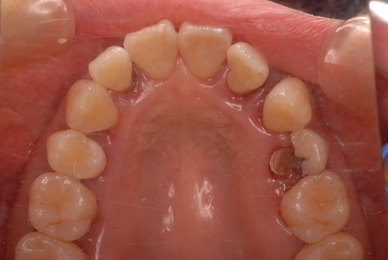

検査をすれば恐ろしいほどの状態だといえるのです。10年後は虫歯と歯周病で残っている歯は何本なのか心配になってきました。

歯磨きではなく、歯の間、そして歯周ポケットと呼ばれる歯と歯肉の間の溝の清掃をできる能力を持つ必要性があるのです。

これができていない状態で何かを被せたり、詰めたりするから再発し加速度的に口の中は崩壊していくのです。